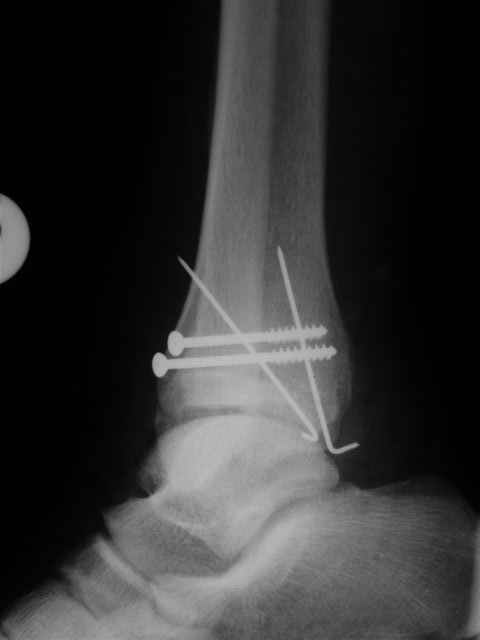

Я предупреждал, что ничего сверхъестественного. Каюсь, что одна из спиц прошла несколько дальше, чем нужно было, но главное - перелом стабилизирован и больной работает суставом в полном объёме, несмотря на представленную раннее травму коленного сустава.